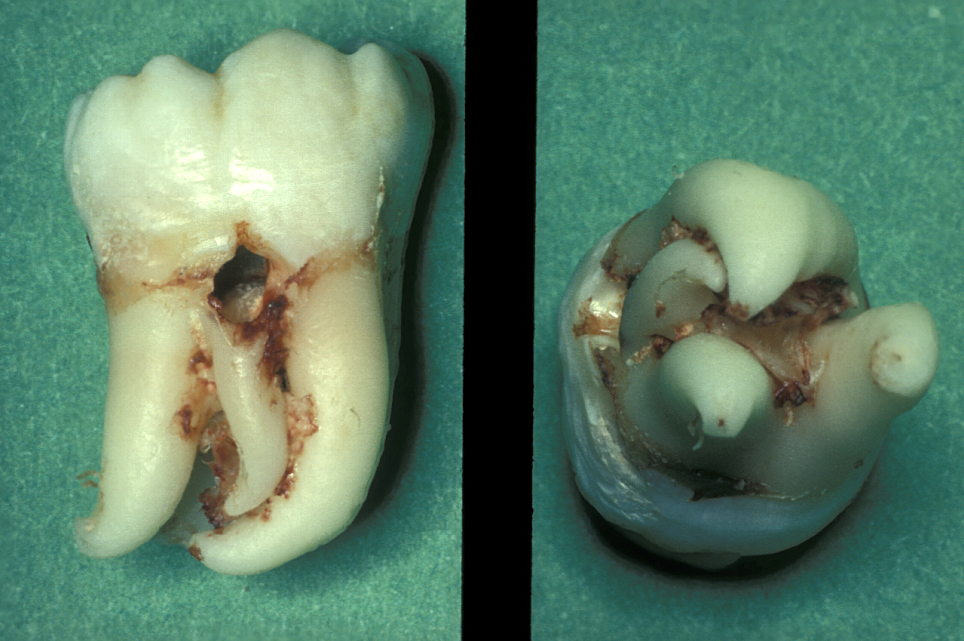

The root pattern (Figure 11) and relationship to the inferior alveolar nerve bundle, to the adjacent second molar, and to bone of the ascending ramus of the mandible can all create problems with simple elevation of third molars. Sectioning the tooth is the safest technique to overcome this. The tooth is decoronated by cutting through the amelo-cemental junction (about 80% through), then the crown is fractured off with an elevator. If the tooth is still resistant to elevation, the roots are separated by cutting through the bifurcation and elevating them individually (Figure 12).